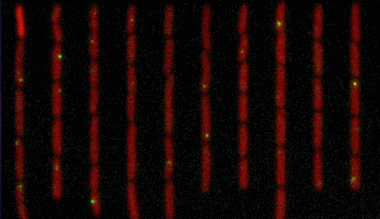

在这些年间,人们不断深入,破译了多条染色体的密码,而6号染色体算得上是迄今为止科学家破译的包含基因最多的染色体之一。

资料显示研究人员对人类的6号染色体超过1.66亿个碱基对进行测序和分析之后,发现了有2190个基因结构,其中1557个位功能基因,约占人类基因总数的6%。此外,其中约130个基因可以导致人出现某些疾病。

6号微小染色体缺失,英国女孩变成“三无人类”

6号染色体上的基因有很多